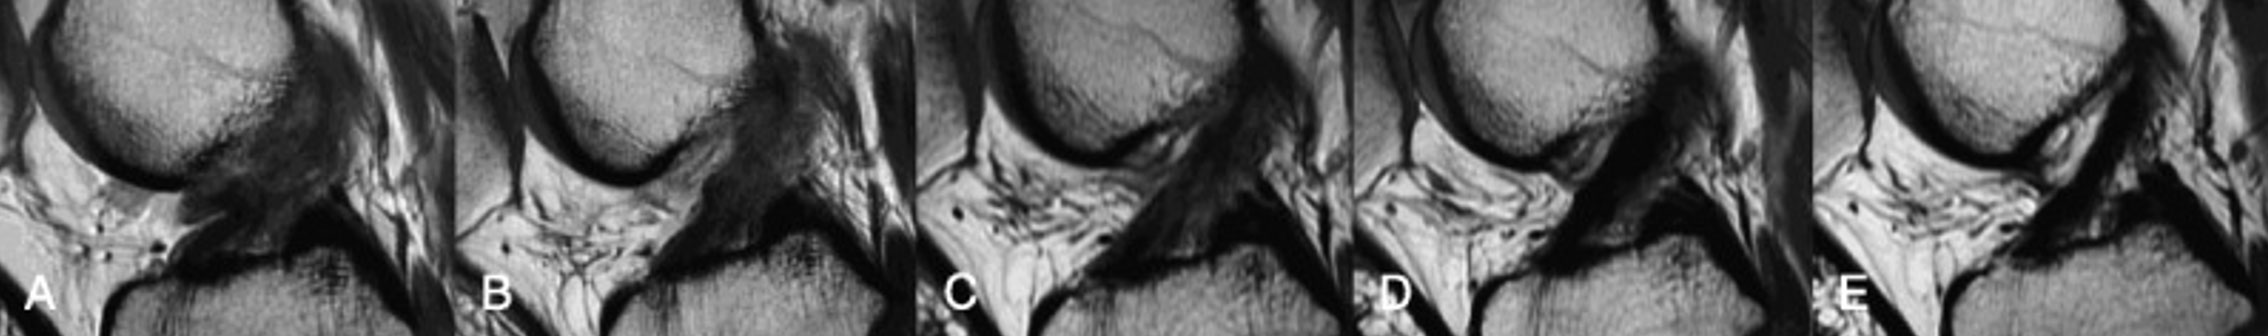

Below is a series of MRI pictures demonstrating ACL healing on MRI scan.(7) The first picture is at time of injury, followed by 2 months, 6 months, 1 year, 3 years post-injury.

MRI pictures demonstrating ACL healing on MRI scan - Brisbane physiotherapist